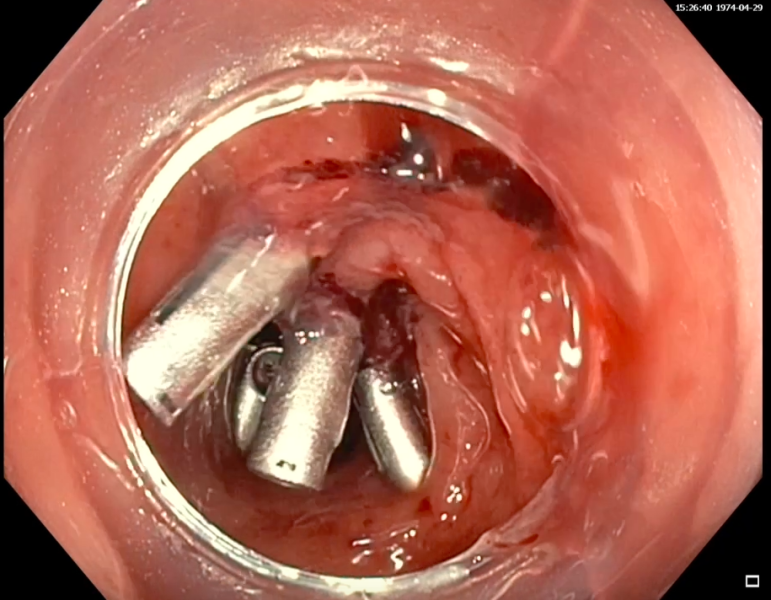

[ 1º Classificado] Look beneath the surface - endoscopic removal of a fishbone completely embedded in the esophageal wall

Vídeo